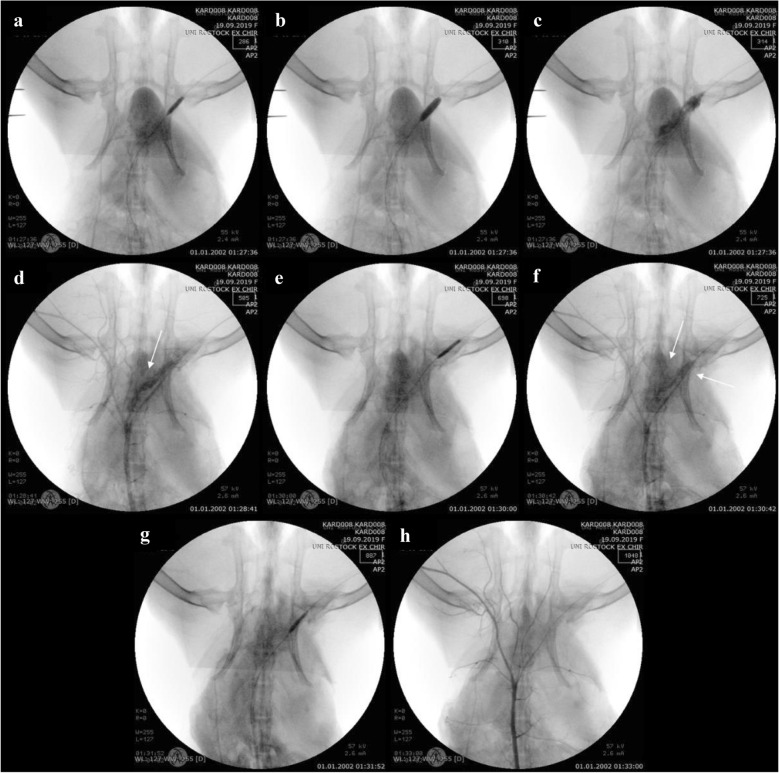

In the third method designed to attain vessel perforation by means of an oversized device, a 4.5 × 12 mm balloon catheter was inserted into the iliac artery (Fig. 4a). To intensify the perforation, the oversized balloon catheter was overdilated and slightly moved proximally (Fig. 4b) until its bursting (Fig. 4c). Massive extravasation of contrast media was the indicative of vessel perforation (Fig. 4d). After the first covered stent implantation (Fig. 4e), the extravasation of contrast media (Fig. 4f) was still visible. However, following a second covered stent implantation (Fig. 4g), the perforation was sealed, with no contrast media leakage detected upon angiography (Fig. 4h).

Fig. 4.

Angiography of the iliac artery perforation by overdilation and the bursting of an oversized balloon catheter. a Placing and dilatation of the oversized balloon catheter. b Dislocation of the balloon catheter after overdilation. c The burst oversized balloon catheter. d Extravasation of contrast media after vessel perforation. e First covered stent implantation. f Leakage of blood from the ruptured vessel after first stent implantation. g Second covered stent implantation. h Verification of the leakage being sealed after stent implantation